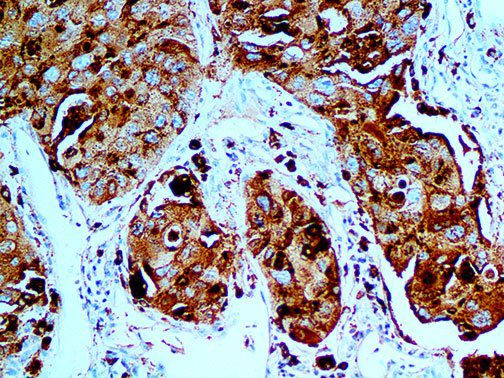

The vast majority of patients with COVID-19 have had a good prognosis, but there are still some critical individuals and even death.10 Most of these critically ill and dead patients do not develop severe clinical manifestations in the early stages of the disease. Some patients only show mild fever, cough, or muscle soreness. These conditions suddenly deteriorate in the later stages of the disease or in the recovery process . Acute respiratory distress syndrome (ARDS) and multiple-organ failure occur rapidly, resulting in death within a short time. Cytokine storm is considered to be one of the major causes of ARDS and multiple organ failure.

Cytokine Storm Syndrome (CSS) is characterized by systemic symptoms and signs derived from a massive and uncontrolled inflammatory response caused by pro- and anti-inflammatory cytokine dysregulation. Viruses, such as Herpes and Epstein-Barr are known to trigger CSS, as is H5N1 influenza. Current literature indicates that SARS-CoV-2 triggers CSS and has been attributed to the severe symptoms’ characteristic of critical patients. CSS in these patients is often fatal, as was the case in the previous SARS and MERS outbreaks.

This activation induces inflammatory monocytes to highly express IL-6, starting a localized and then systemic cascade effect that results in hyperproduction of IL-6, which accelerates the inflammatory process. Because IL-6 also increases vascular permeability, excessive levels cause blood vessels to become very leaky. This, along with clotting factors released from vascular endothelial cells, stimulates the coagulation cascade, resulting in microthrombosis (tiny clots), which leads to ischemia and tissue death of the kidney, intestines, heart, liver, brain and extremities.